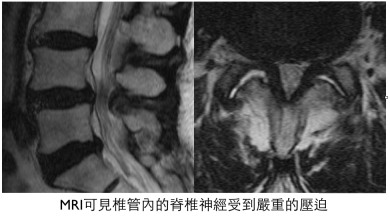

X光雖然可以看到脊椎退化的一些證據,例如骨刺的形成、椎間盤高度減低、退化性椎間滑脫等,但因看不到神經組織,所以無法得到確切的診斷,也無法評估椎管狹窄及神經組織受壓迫的嚴重度。電腦斷層掃描 (computed tomography, CT) 或核磁共振造影 (magnetic resonance imaging, MRI) 才可以達到上述的目的。兩種檢查各有優缺點,孰優孰劣在文獻上尚未有定論,雖然各國學者都同意同時有兩種檢查的影像分析是最好的選擇(美、日、韓等國都是如此),但在本國有礙於中央健保局的規範,兩者只能擇一進行;本人較偏好核磁共振造影,因其對神經組織的成像遠較電腦斷層清楚,比較容易評估神經組織受壓迫的部位。但需特別注意,有些病人因裝置有心律節律器或其他因素無法接受核磁共振造影,此時建議住院接受脊髓造影 (myelography) 合併電腦斷層掃描,也可得到相當清楚的影像評估。